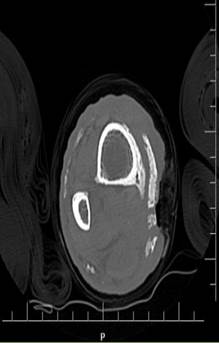

Inicialmente consultó en el hospital local, donde iniciaron manejo antibiótico con clindamicina y ampicilina-sulbactam, con posterior exposición ósea y miasis, por lo que remitieron a una institución de mediana complejidad, donde administraron una dosis única de ivermectina, con curación completa de la miasis. Sin embargo, hubo persistencia de la exposición ósea por lo que se decidió remitir a una institución de alta complejidad para manejo multidisciplinario, con el diagnóstico de sospecha de osteomielitis de tibia. Al ingreso a la institución se realizó una radiografía AP y lateral de la pierna derecha donde se apreciaba una zona calcificada en la región medial de la extremidad, la cual se puede observar en las Figuras 2 y 3.

Al examen físico, presentaba cambios de coloración en la piel de ambas extremidades, pérdida de los folículos pilosos, una zona indurada en toda la cara medial de ambas piernas (de la cual el paciente no se había percatado), pérdida de los pulsos pedios y tibiales a la palpación, con pulsos poplíteos filiformes. Se solicitó una ecografía doppler de miembro inferior derecho que reportó una insuficiencia venosa superficial troncular de la safena mayor derecha segmentaria, con permeabilidad del sistema profundo; y además, se solicitó una tomografía computarizada de miembro inferior derecho, donde se apreció en los tejidos blandos una extensa calcificación en el plano entre el tejido celular subcutáneo y la fascia muscular superficial, especialmente en la cara medial y anterior, sugestivo de una OH con reacción perióstica de la misma (Figura 4 y 5). Por lo anterior, se sospechó que el paciente cursaba con una osteomielitis de la zona osificada, sin compromiso de la tibia. Fue llevado a cirugía para realizar lavado y curetaje óseo, con toma de cultivos y de biopsia. Trás 72 horas de cultivo se obtuvo crecimiento de Morganella morganii sensible (cefepime sens <=1, amikacina sens <=2, gentamicina sens <=1, TMP-SMX sens <=20). Recibió manejo antibiótico guiado por el antibiograma con trimetroprim-sulfametoxazol por 6 semanas, con adecuada evolución clínica por lo que fue dado de alta de la institución. Se recibió el resultado de la biopsia, donde reportaron tejido óseo maduro con infiltrado central linfoplasmocitario y polimorfonuclear neutrófilo en menor cantidad, compatible con una osteomielitis.

Figura 5 Corte axial en tomografía axial computarizada simple de pierna derecha.